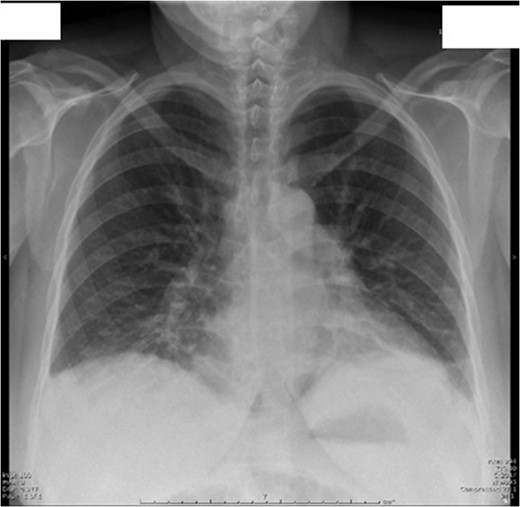

On Day 1 post surgery she was noted to be tachycardic, febrile and hypertensive with a drop in saturation 92–93% on room air along with abdominal pain. Her differential diagnosis included atelactesis, pulmonary embolism and endometriosis (Fig. 1). On examination she had good bowel sounds, was passing flatus but had not opened her bowels. On Day 2 she had localized right lower quadrant tenderness with raised inflammatory markers of CRP 163, WCC 21 × 109/l and neutrophil count 17 × 109/l. The computed tomography (CT) scan of her abdomen/pelvis (A/P) showed evidence of ileus with dilated loops of bowel (Fig. 2).

Day 1 postoperative chest X-ray shows evidence of mild atelactesis.